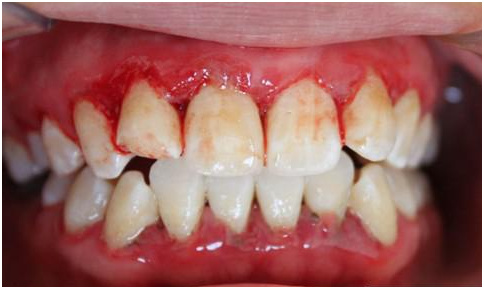

牙龈炎是何方神圣呢,如果你常在刷牙或咬硬物时牙龈出血,牙龈附近的牙面有明牙石堆积,牙龈颜色是暗红色或鲜红色,龈乳头圆钝肥大,好吧,十有八九是牙龈炎了,如果加之口腔专科检查:牙龈松软缺乏弹性,探诊后出血,龈沟液量增加,可以100%确定你有牙龈炎了。

牙龈炎看起来挺严重呢,不,更严重的是牙周炎。除了上述牙龈炎症状外,当还有牙周袋大于3mm,牙齿邻面附着丧失大于1mm,牙齿X线片显示压槽骨有吸收,严重者甚至有口臭、溢脓、牙齿松动等,这些就可以确诊牙周炎了。看到下面这张图,是不是有一种“使我不得开心颜”的惆怅呢,还有下面的X牙片,让我想起了《千年泪》中“摇摇欲坠,不只你的泪”,这里摇摇欲坠的还有你的牙。